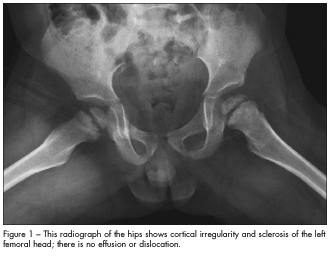

Radiographs of the hips shown.

This patient’s radiographs showed cortical irregularity and sclerosis of the left femoral head, without effusion or dislocation (Figure 1). Because these findings may also represent Legg-Calvé-Perthes disease, MRI was performed to confirm the diagnosis of Meyer dysplasia (Figure 2).